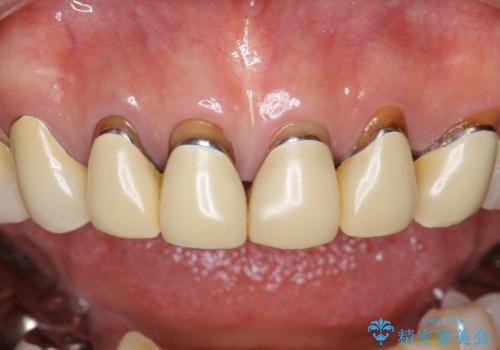

- 前歯のセラミック治療から4年半経過した患者様です。

4年ぶりに来院して下さいました。

治療した上の前歯6本は全く問題なく、「獅子舞みたいだった前歯を綺麗にして下さってありがとうございました!」と再度お礼を言って下さいました。

4年半前のクラウン装着時と変わらず、まるで天然歯のように自然に見えました。

患者様の良好なセルフケアと精密な適合の良いクラウンにより、歯肉の腫脹や退縮も認められませんでした。